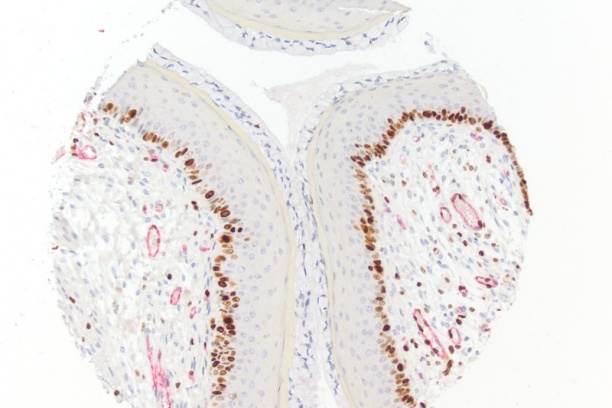

- Research histology including, immunohistochemistry and novel antibody development